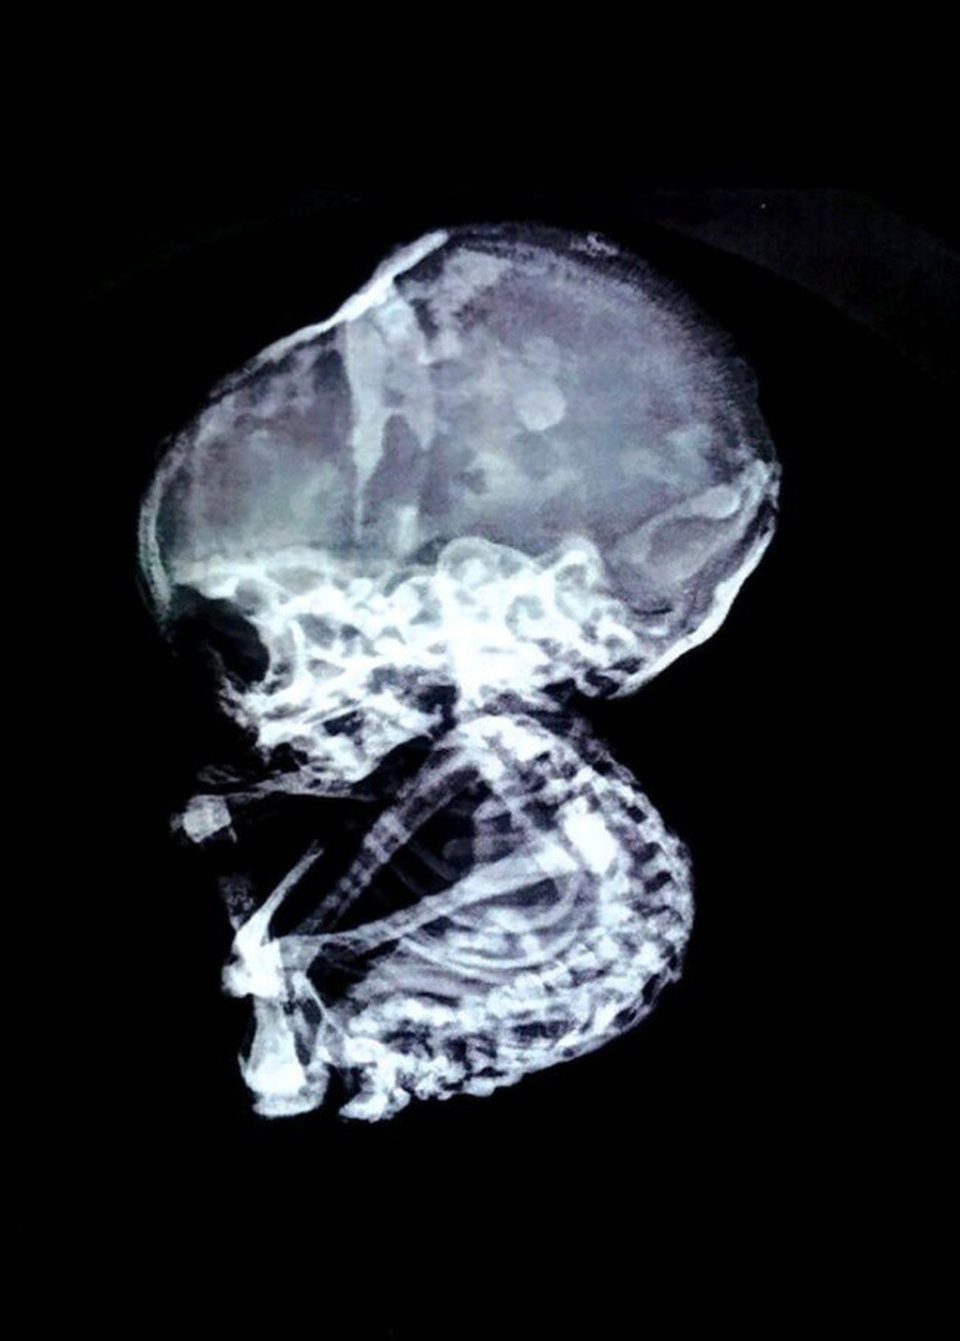

“Chụp chiếu cho thấy đường ruột cô ấy bị tắc nghẽn nghiêm trọng. Ống dẫn thức ăn bị một vật có cấu trúc giống như đá chèn ép. Thông thường bào thai chết lưu sẽ bị thối rữa, có thể gây nhiễm trùng cho cơ thể người mẹ nhưng trong trường hợp này, thai nhi đã tự ướp xác, tích tụ muối và hóa đá”, tiến sĩ Nilesh Junankar chia sẻ.

Vị bác sĩ phẫu thuật nội soi cũng cho biết các trường hợp bào thai hóa đá là vô cùng hiếm gặp, chỉ có khoảng 300 trường hợp được ghi chép trong lịch sử. Những trẻ sơ sinh hóa đá thường là kết quả của việc mang thai ngoài tử cung và không có cách nào rời khỏi cơ thể người mẹ.

Thai nhi hóa đá khi 4 tháng tuổi và đã phát triển tương đối đầy đủ trong bụng mẹ